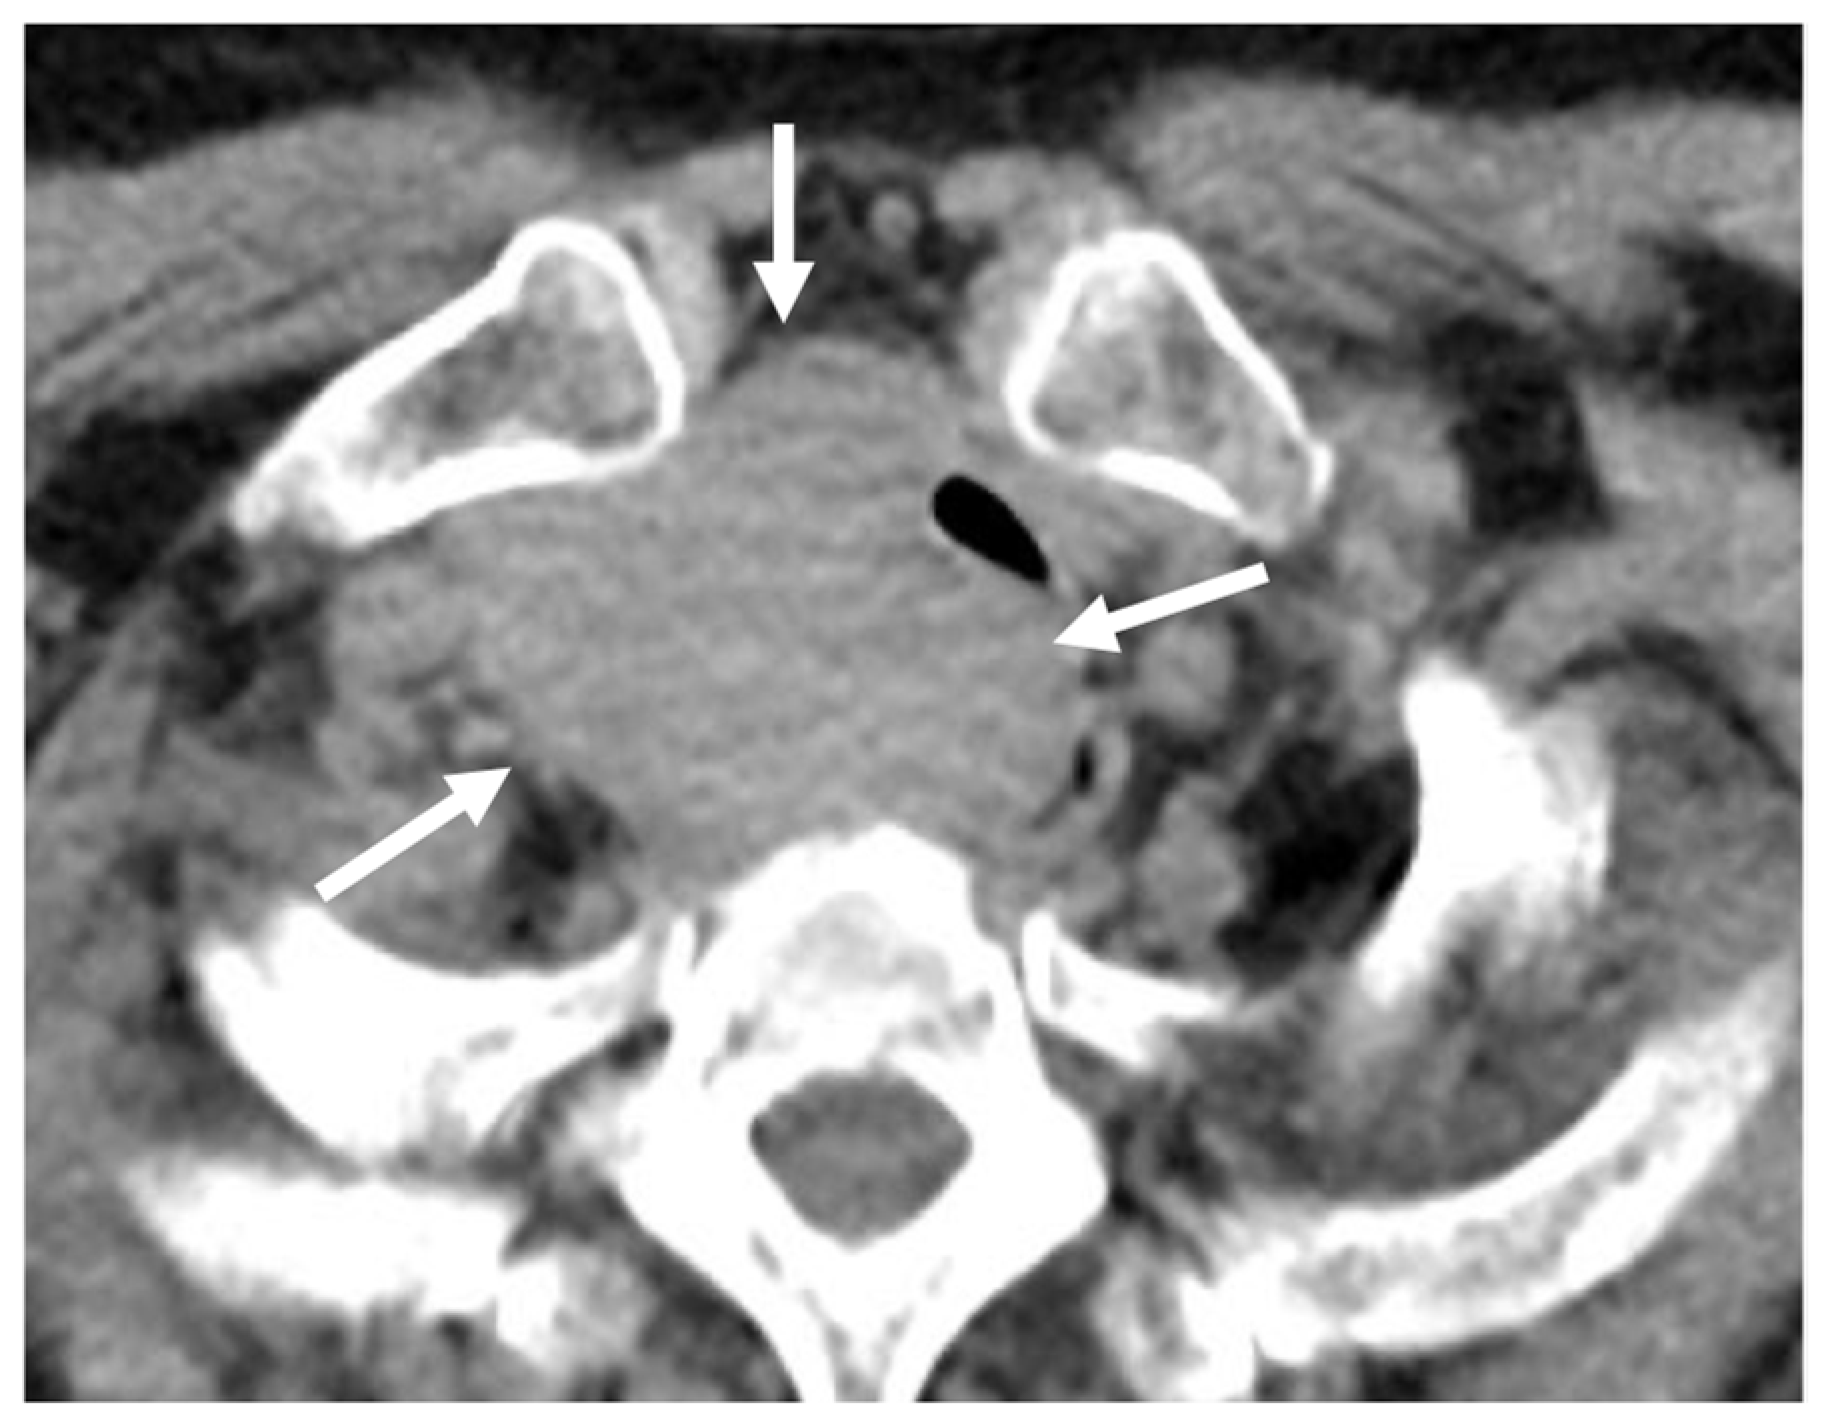

5.2. Breast